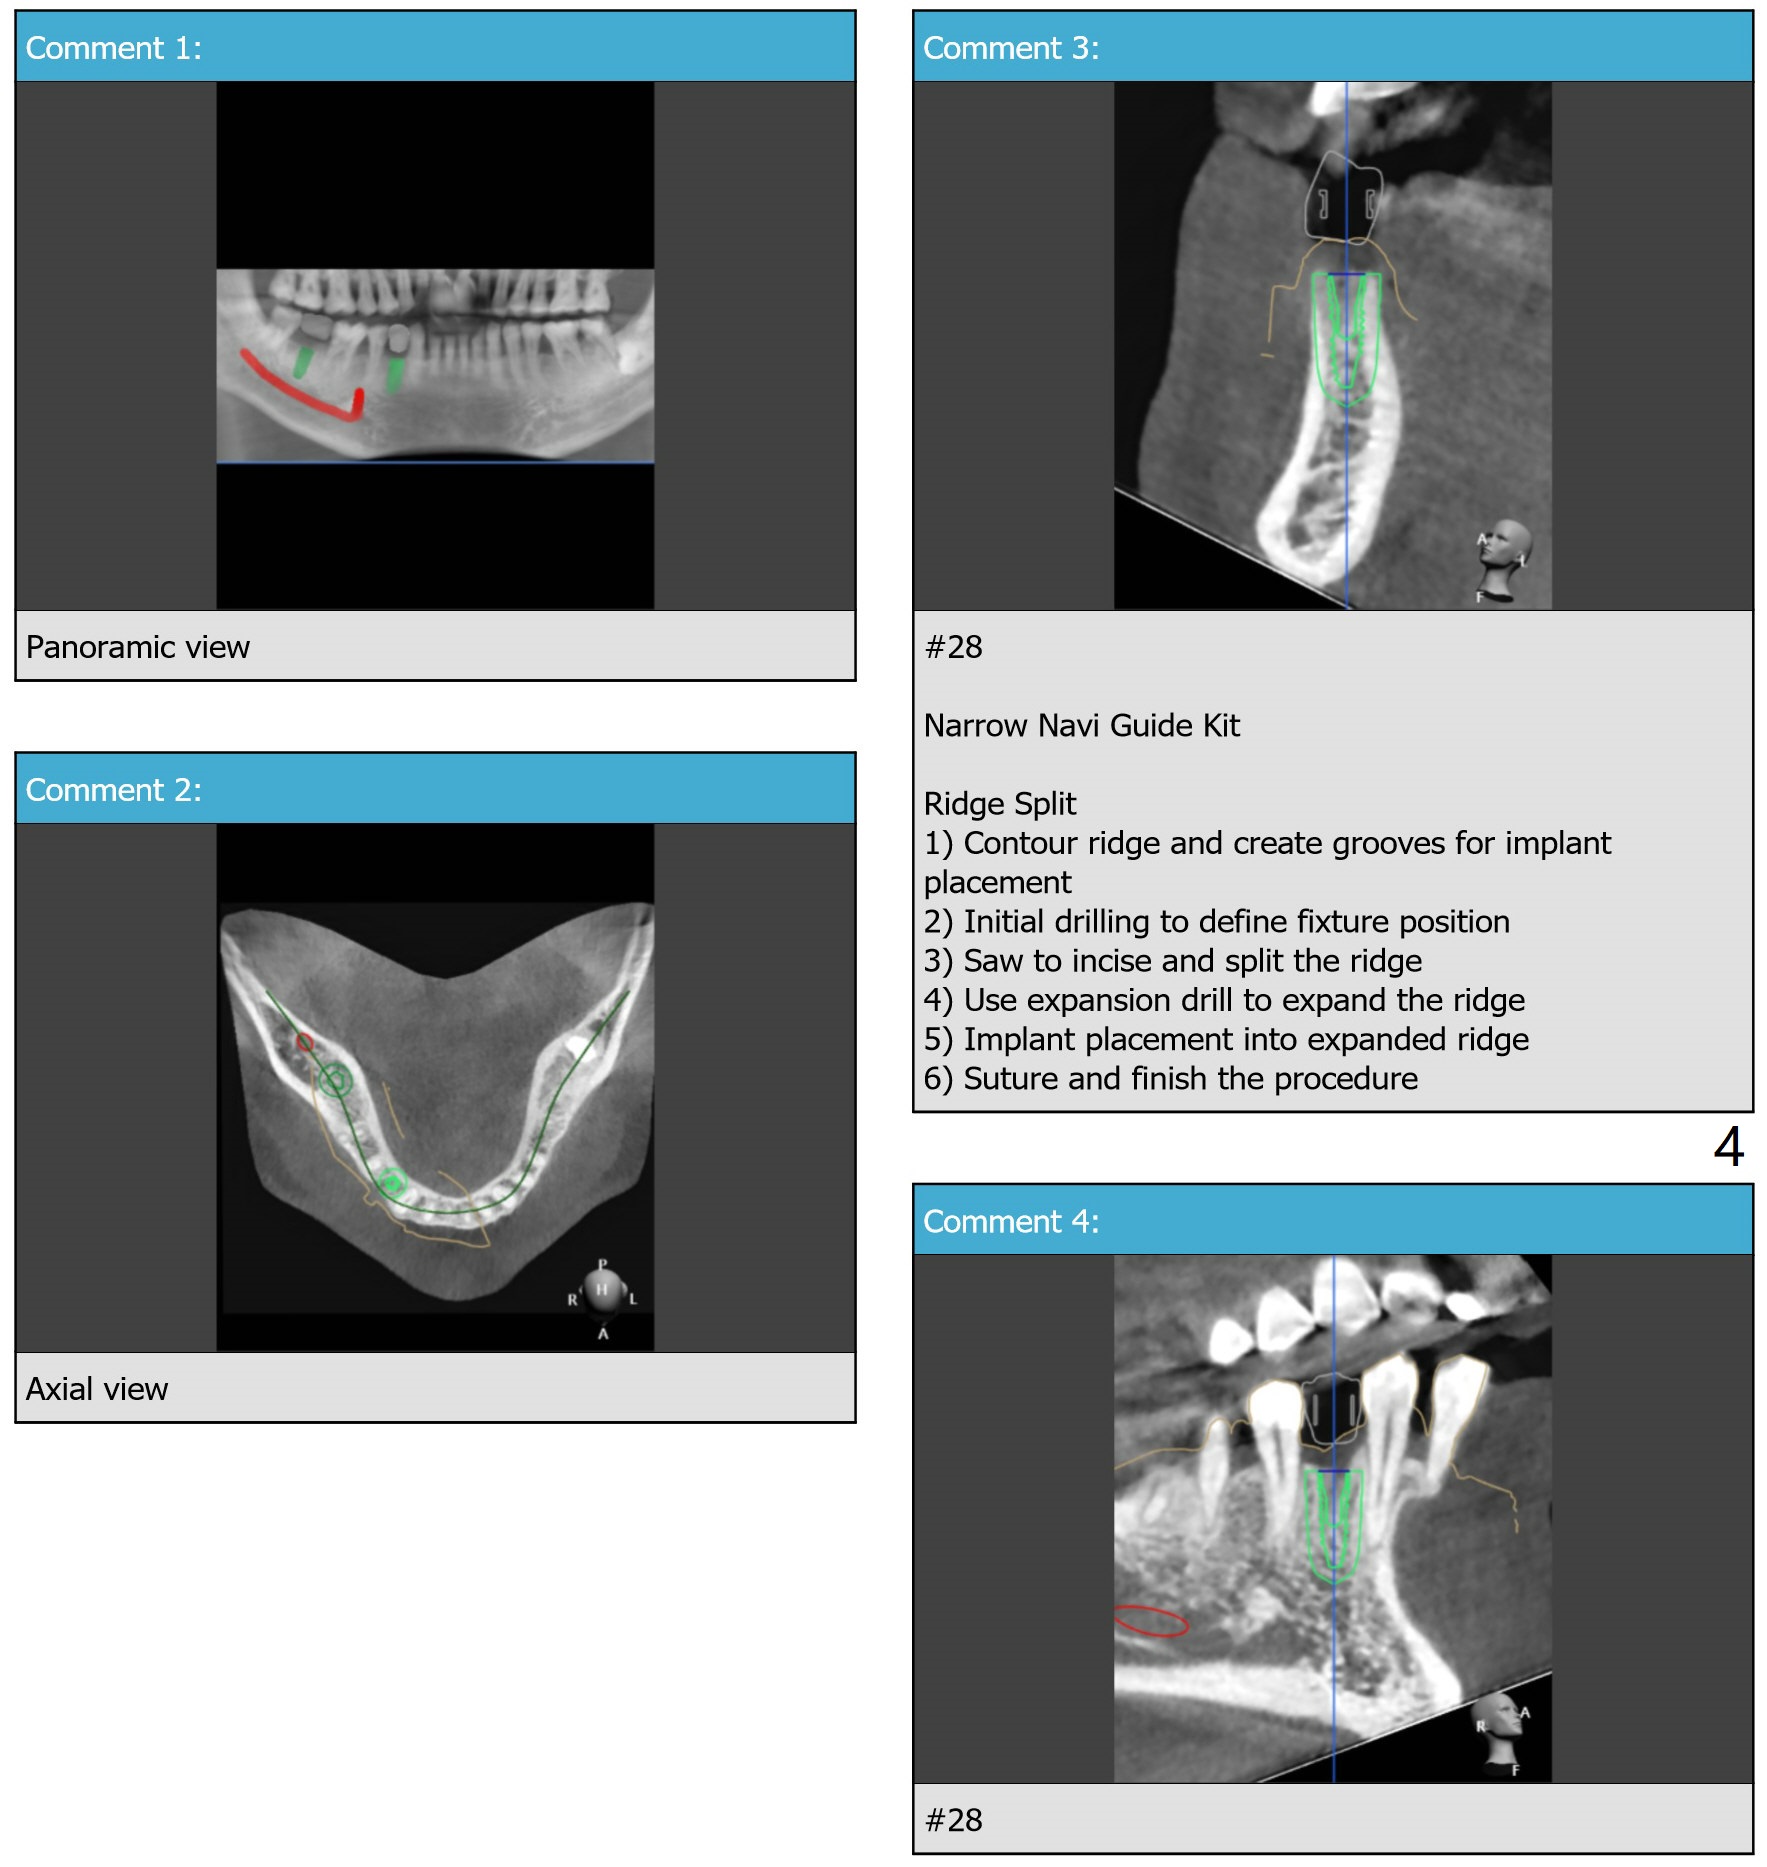

For buccal concavity at #28 to be fixed with bone expansion (DIO Bone Expanders Kit), surgical guide has modification (Fig.5,8).